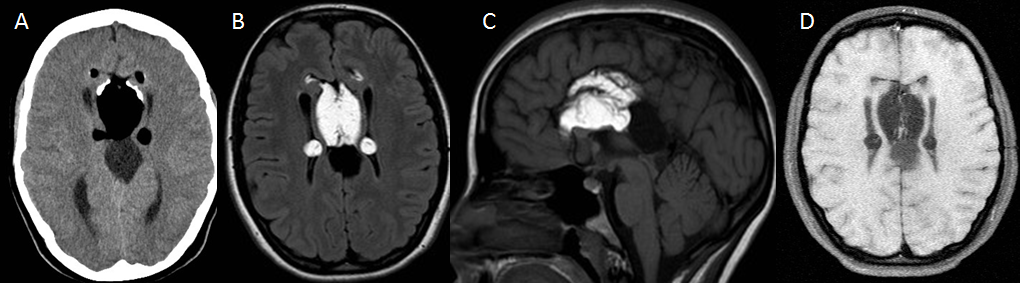

Mujer de 37 años con amenorrea que ingresa por poliuria y polidipsia. Antecedentes de anemia hemolítica no inmune, esplenectomizada. En tratamiento con metformina.

Depósito de hierro en la hipófisis secundario a hemocromatosis secundaria produciendo un hipogonadismo hipogonadotrófico.

La hemocromatosis secundaria es una enfermedad caracterizada por el depósito de hierro en el hígado y en otros órganos. El hierro se puede depositar en la hipófisis, ocasionando un hipogonadismo hipogonadotrofo.

En esta paciente se observa, además del depósito de hierro en la hipófisis, una hiperintensidad de señal de los ganglios basales, hallazgos que pueden ver en la degeneración hepatocerebral adquirida.

Tras la realización de esta RM hipofisaria se le realizaron a la paciente RM de abdomen y de corazón, existiendo también depósito de hierro hepático, pancreático y miocárdico, con diabetes mellitus secundaria.